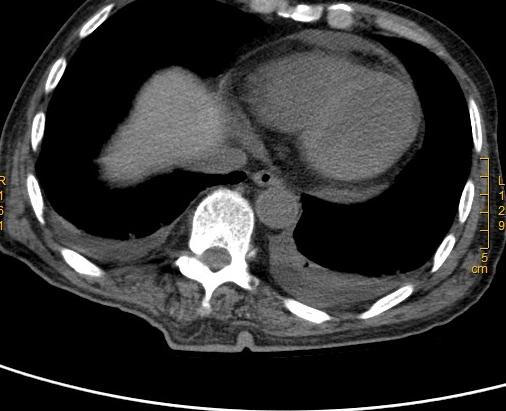

心包积液

甲减导致的心包积液又被称为黏液性水肿心包积液,由于甲减患者的甲状腺激素分泌不足,身体代谢降低,心脏器官代谢也随着降低,这时心包膜血管通透性增加,血管内液体和黏蛋白漏出,就会引发心包积液,从而导致甲减性心脏病。